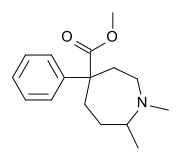

Ketobemidones

Structures